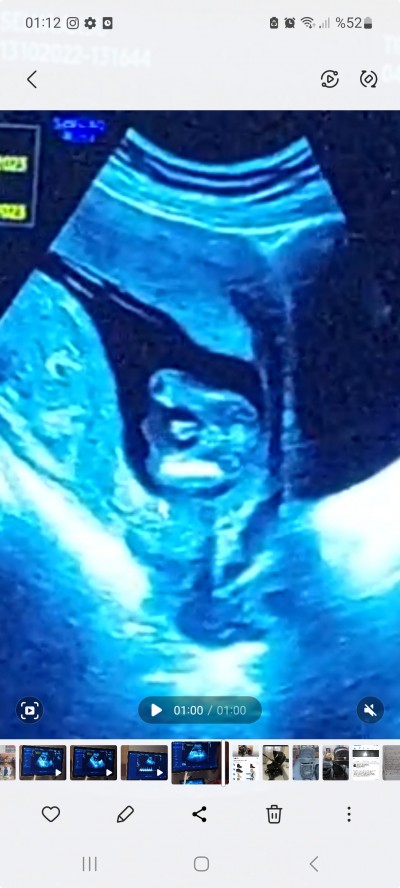

14+3 ultrason resmi

Gebelik haftası 16+2

Burdaki buyuklukten dolayi kordonla karisma ihtimali varmi acaba diye dusunuyorum

Onde "ık>ntısı var ama haftasina gore buyuk duruyor kordonla karisma ihtimali olabilirmi dusundum

Onde cikintısı var ama haftasina gore buyuk duruyor kordonla karisma ihtimali olabilirmi dusundum

Erkek dedi ama hem cok hareketli zor bakti  hemde cikinti bana buyuk gorundu o yuzden emin olamiyorum